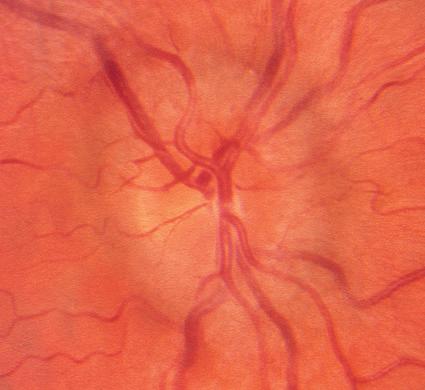

Bilateral disc swelling

10. Bilateral disc swelling could be papilledema (disc swelling due to raised intracranial pressure). The first investigation should be urgent (same-day) magnetic resonance imaging (MRI) plus magnetic resonance venography (MRV) to exclude a brain tumor or dural venous sinus thrombosis (see p. 120) (Fig. 1.10).

1.10 This 38-year-old man presented to an ophthalmic emergency department complaining of blurred vision and headaches. Examination revealed visual acuity 20/20 right and left and bilateral moderate disc swelling A, B. Because vision was good and there were “no other neurologic signs”, the patient was allowed to go home and was scheduled for neuro-imaging as an outpatient. Two days later, while driving, the patient experienced a generalized seizure, resulting in severe injuries to himself and another driver. MRI revealed a brain tumor which was found at surgery to be an astrocytoma. For how to safely manage disc swelling with normal vision, see p. 110.